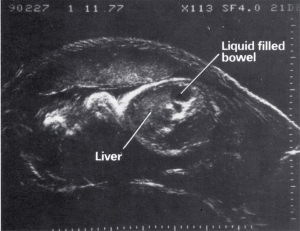

- Fetal anatomy

| 1980 | Demonstration of fetal lung, liver and bowel maturation by grey scale ultrasound |

| 1970 | Introduction of grey scale ultrasound, improving dramatically the demonstration of normal and abnormal structures in the fetus, placenta and mother |